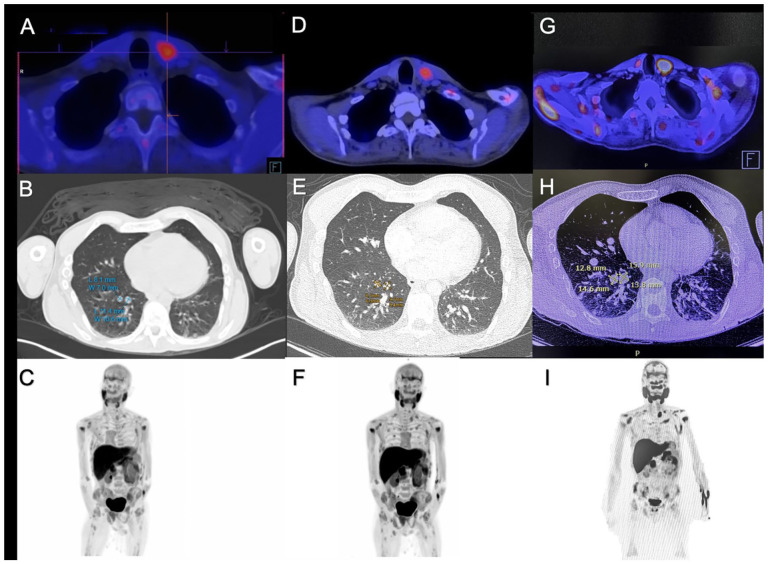

甲状旁腺癌(PC)是一种罕见的内分泌恶性肿瘤,其特点是严重的高钙血症和高复发率。我们报告一名34岁男性慢性肾脏疾病患者的病例,他发展为病理性骨折和继发于PC的进展性肺转移。遗传分析揭示了CDC73基因的致病变异,表明遗传易感性。手术切除后,患者出现早期生化复发。最初使用双膦酸盐、地诺单抗和cinacalcet治疗可暂时控制高钙血症。放射学进展后,开始lenvatinib治疗,导致9个月的生化控制和局部疾病和肺转移的稳定。然而,由于获取途径有限,停用denosumab和cinacalcet导致严重高钙血症复发和疾病进展,需要停用lenvatinib并过渡到姑息治疗。该病例强调了PC的诊断和治疗挑战,突出了lenvatinib等靶向治疗在晚期疾病中的潜在作用,并强调了持续获得基本治疗的至关重要性。

Parathyroid carcinoma (PC) is an exceptionally rare endocrine malignancy characterized by severe hypercalcemia and high recurrence rates. We present the case of a 34-year-old male with chronic kidney disease who developed pathological fractures and progressive pulmonary metastases secondary to PC. Genetic analysis revealed a pathogenic variant in the CDC73 gene, indicating a hereditary predisposition. Following surgical resection, the patient experienced early biochemical relapse. Initial management with bisphosphonates, denosumab, and cinacalcet achieved temporary control of hypercalcemia. Upon radiological progression, lenvatinib therapy was initiated, resulting in 9 months of biochemical control and stabilization of both local disease and pulmonary metastases. However, discontinuation of denosumab and cinacalcet due to limited access led to a relapse of severe hypercalcemia and disease progression, necessitating the cessation of lenvatinib and transition to palliative care. This case underscores the diagnostic and therapeutic challenges of PC, highlights the potential role of targeted therapies like lenvatinib in advanced disease, and emphasizes the critical importance of sustained access to essential treatments.